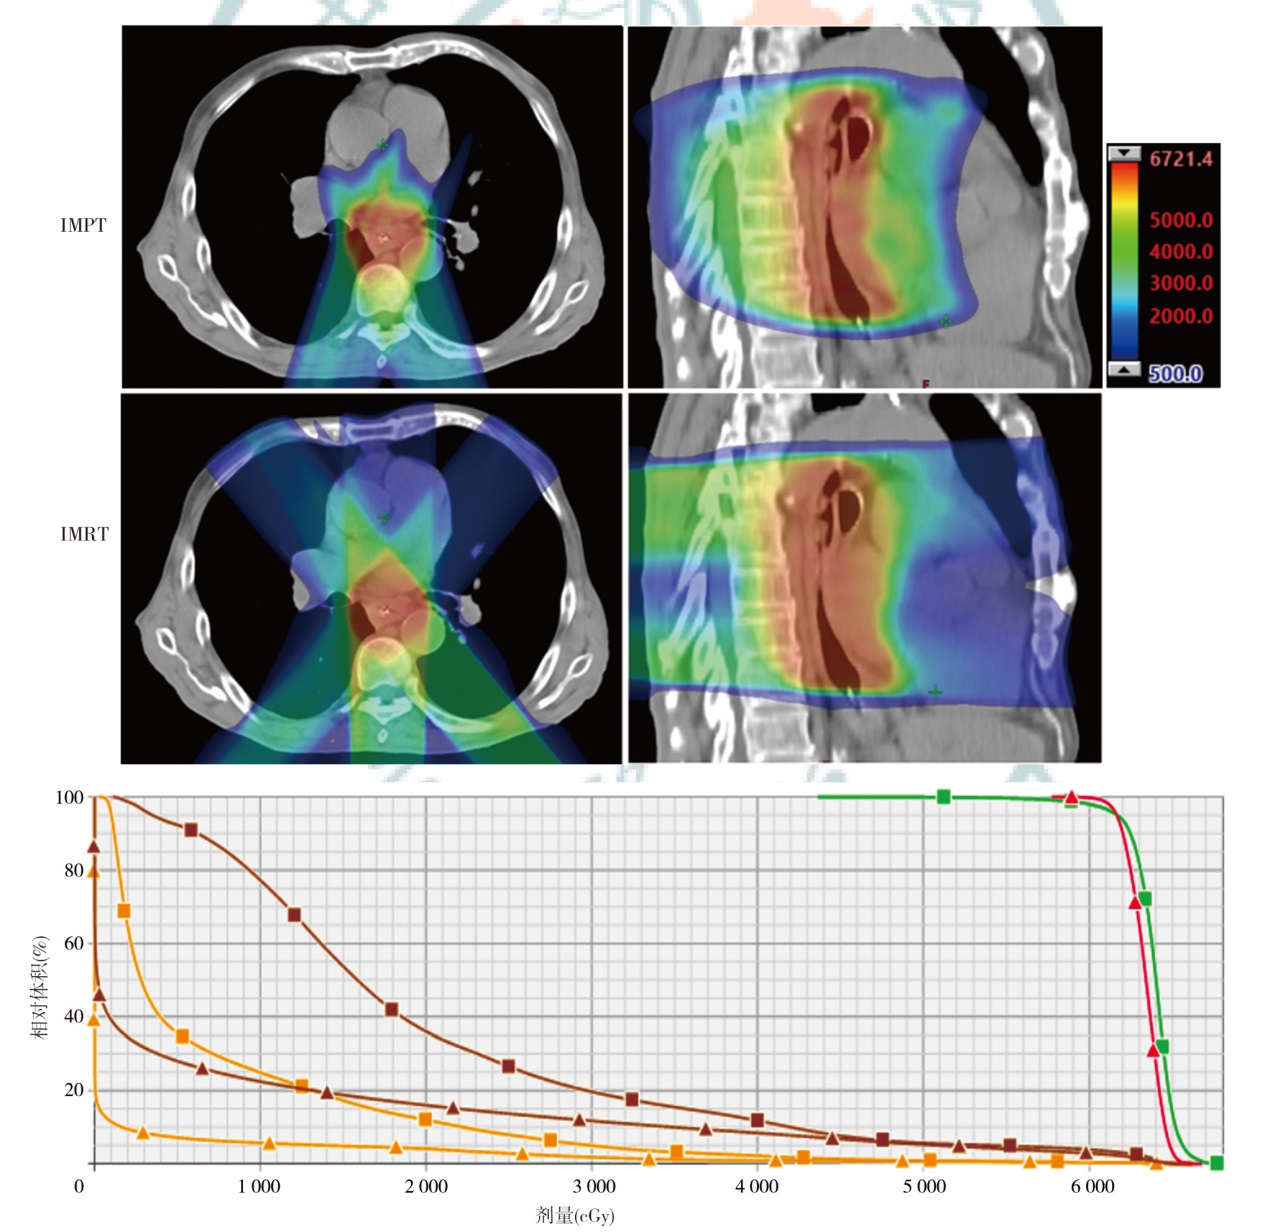

Objective To explore the dosimetric characteristics of proton radiotherapy plan and photon radiotherapy plan for esophageal cancer. Methods Four patients who were admitted to Shandong Cancer Hospital and Institute from January 2024 to April 2024 with esophageal cancer (cervical, middle thoracic and total esophageal tube, as well as the lymphatic drainage areas involved) and required radiotherapy were selected as the research subjects. Intensity modulated proton therapy (IMPT) and intensity modulated radiation therapy (IMRT) plans were designed respectively based on the clinical target volume and the dose constraints for organs at risk (OARs). Dosimetric parameters, including conformity index (CI), homogeneity index (HI), gradient index (GI) for target coverage, as well as OARs dosimetric parameters were evaluated. The volume of additional dose deposition in the body was compared by assessing regions receiving 10%, 30%, and 50% of the prescription dose. Results For all four cases, IMPT plans yielded lower HI values (0.12, 0.10, 0.06, and 0.08) than IMRT plans (0.15, 0.13, 0.10, and 0.11), and the GI values of IMPT plans (3.11, 3.21, 2.43, and 2.72) was lower than IMRT plans (4.52, 5.14, 3.09, and 3.92). Moreover, the CI of the IMPT plans (0.59, 0.60, 0.77, and 0.72) was inferior to IMRT plans (0.81, 0.77, 0.91, and 0.85). Compared with the IMRT plans, in the whole lung dose indicators of the IMPT plans for the 4 patients, V5 decreased by 34.1%, 55.0%, 79.7% and 60.3%, respectively; V20 decreased by 48.3%, 43.9%, 65.8% and 40.8%, respectively, and Dmean decreased by 43.4%, 57.2%, 76.2% and 45.4%, respectively. V30 of the heart decreased by 36.2%, 45.3%, 40.1% and 52.4%, respectively, and Dmean of heart decreased by 96.6%, 57.9%, 58.5% and 55.3%, respectively. For the middle and lower thoracic target area, the liver was significantly protected in the IMPT plan (Dmean decreased by 76.0% compared with the IMRT plan). In terms of the additional dose deposition in the patient's body, IMPT plans reduced the volumes receiving 10%, 30% and 50% of the prescription dose by 45.0%-61.4%, 41.2%- 61.8% and 34.8%-61.6%, respectively, compared with the IMRT plans. Conclusions By comparing the dosimetric parameters of IMPT and IMRT plans for 4 cases of esophageal cancer, the IMPT plans have advantages in reducing the doses to lung tissue, heart, and liver, and can also reduce additional dose deposition in the patient's body.